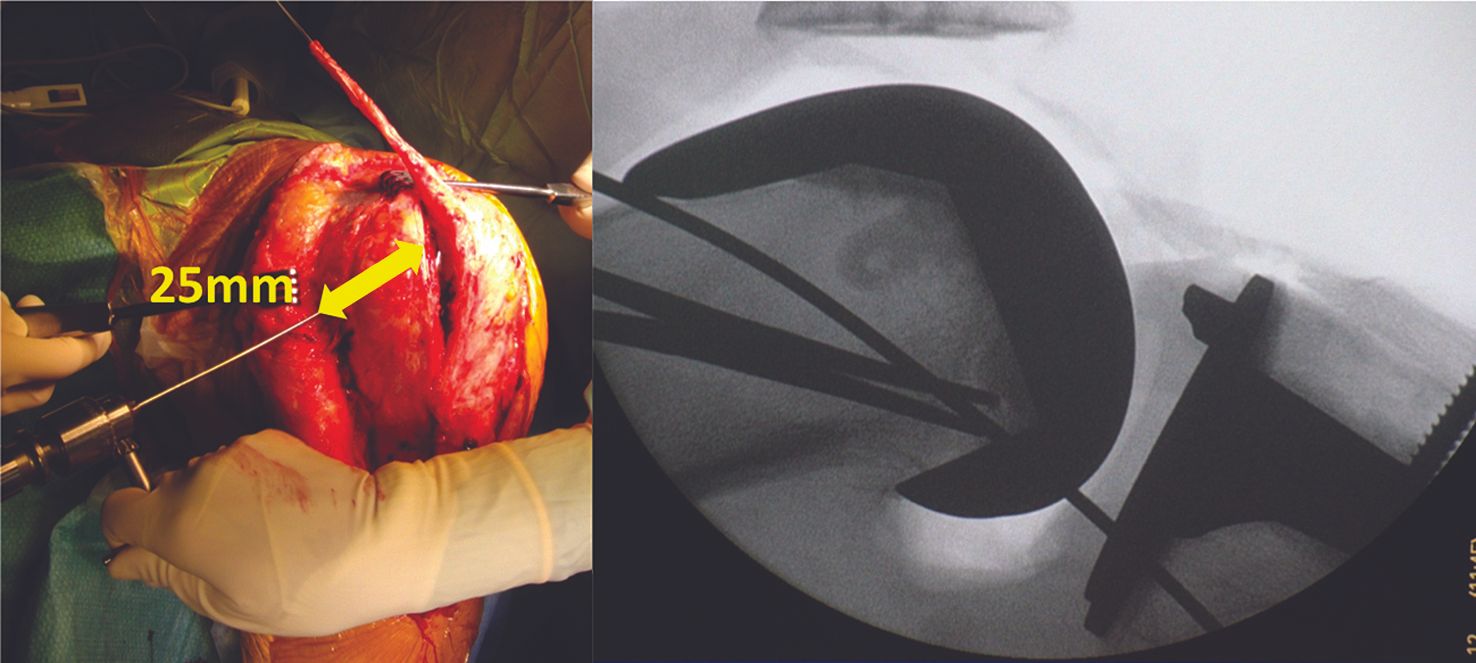

(Figs. 5–10)

We prefer to reconstruct the MPFL using a strip of quadriceps tendon still pedunculated to the upper pole of the patella. This technique appears to have lower patellar morbidity because it avoids the need to make tunnels or impact an anchor into a bone that may already have been weakened by the implant of the patellar component with its three posts.

We use a strip that is 1cm wide, 10cm long and 5mm thick, harvested from the mid third of the quadriceps tendon, taking care to preserve continuity. The distal end is left pedunculated to the patella. The free end of the graft is then prepared with a suture, 25mm along.

Femoral fixation is achieved in exactly the same way as for a MPFL on a native knee: a blind tunnel is made at the isometric point [20] above the adductor magnus tubercle, either using the same approach or by making a counter incision a few millimetres opposite.

The graft is passed outside the capsule. Finally, graft tension is adjusted at 30° of flexion. The patella must be centred and mobile, but not to the point of allowing dislocation. Make sure the patella is not too tight medially. Lateral movement of 7–9mm is recommended. The graft is then fixed with a resorbable interference screw.